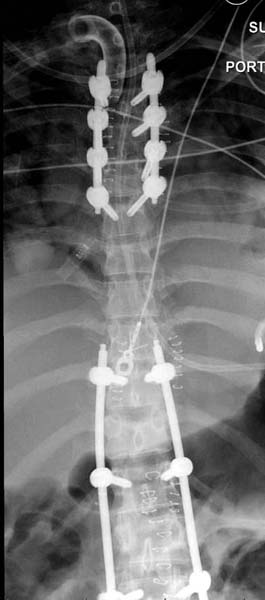

Перелом позвоночника и боковую компрессию таза отнесли к стабильным переломам и не стали форсировать события до лучших времен...

После спадения отека на стопе произведена фиксация тарана. Кстати, коллеги пересмотрели первоначальную консультацию по позвоночнику и на двух уровнях провели фиксацию. Из-за длительного постельного режима без нагрузки таз не стали оперировать...